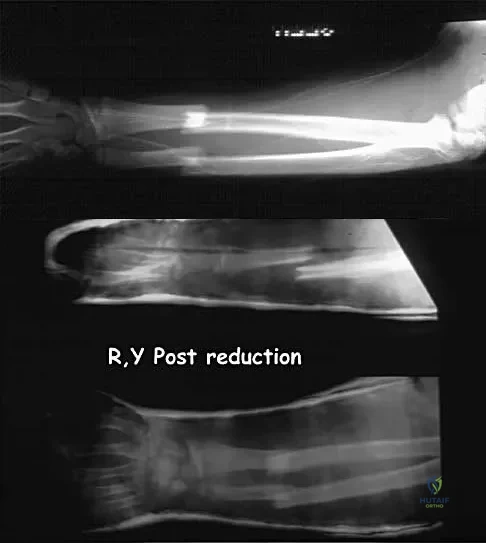

A 23-year-old woman sustains an injury to her right hand after falling off her snowboard. Examination reveals that she has difficulty moving her fingers. A radiograph and a clinical photograph are shown in Figures 8a and Figure 8b. Management should consist of

The radiograph reveals oblique fractures of the third and fourth metacarpals. The rotational component of the fracture displacement is well visualized on the clinical photograph, which shows scissoring of the middle finger over the ring finger. The fracture obliquity results in rotational deformity that cannot be adequately maintained and held by closed treatment. The treatment of choice is open reduction and internal fixation. Stern PJ: Fractures of the metacarpals and phalanges, in Green DP, Hotchkiss RN, Pederson WC (eds): Green's Operative Hand Surgery, ed 4. Philadelphia, PA, 1999, pp 711-771. Freeland AE, Benoist LA, Melancon KP: Parallel miniature screw fixation of spiral and long oblique hand phalangeal fractures. Orthopedics 1994;17:199-200.